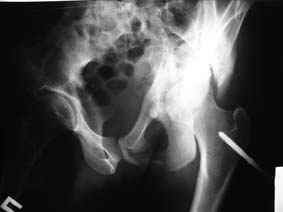

Все-таки надо бы начать не с КТ, а с обзорного снимка таза и косых проекций впадины.

Это обзорные и косые снимки

С уважением,

Привет, Леонид. Оскольчатый высокий двухколонный перелом в такие сроки трогать не надо, т.к. это про такие переломы сказано: "кто с ножом на Ж. пойдет тот в ней и останется...".